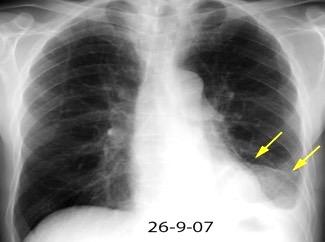

Marzo 2014: Perforación longitudinal distal secundaria a episodio de vómito (síndrome de Boerhaave). Derrame pleural izdo. que evoluciona a empiema.

Wang C-T et al. Tension hydropneumothorax in a Boerhaave syndrome patient: A case report . World J Emerg Med, 2021. Katabathina V et al. Nonvascular, nontraumatic mediastinal emergencies in adults:a comprehensive review of imaging findings. Radiographics. 2011.